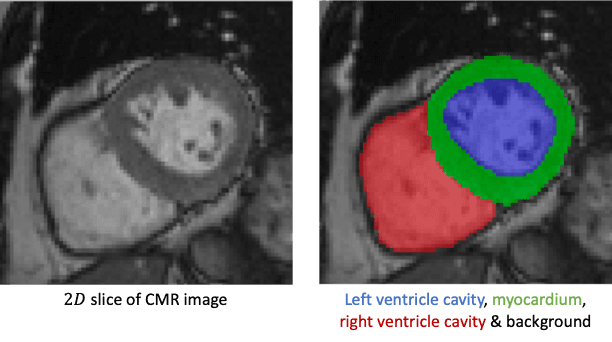

2025Custom model for left ventricle segmentation in cardiac MRI. Based on a Kaggle-style challenge (IMA205: Apprentissage pour l'image et la reconnaissance d'objets).

Custom model for left ventricle segmentation in cardiac MRI. Based on a Kaggle-style challenge (IMA205: Apprentissage pour l'image et la reconnaissance d'objets).